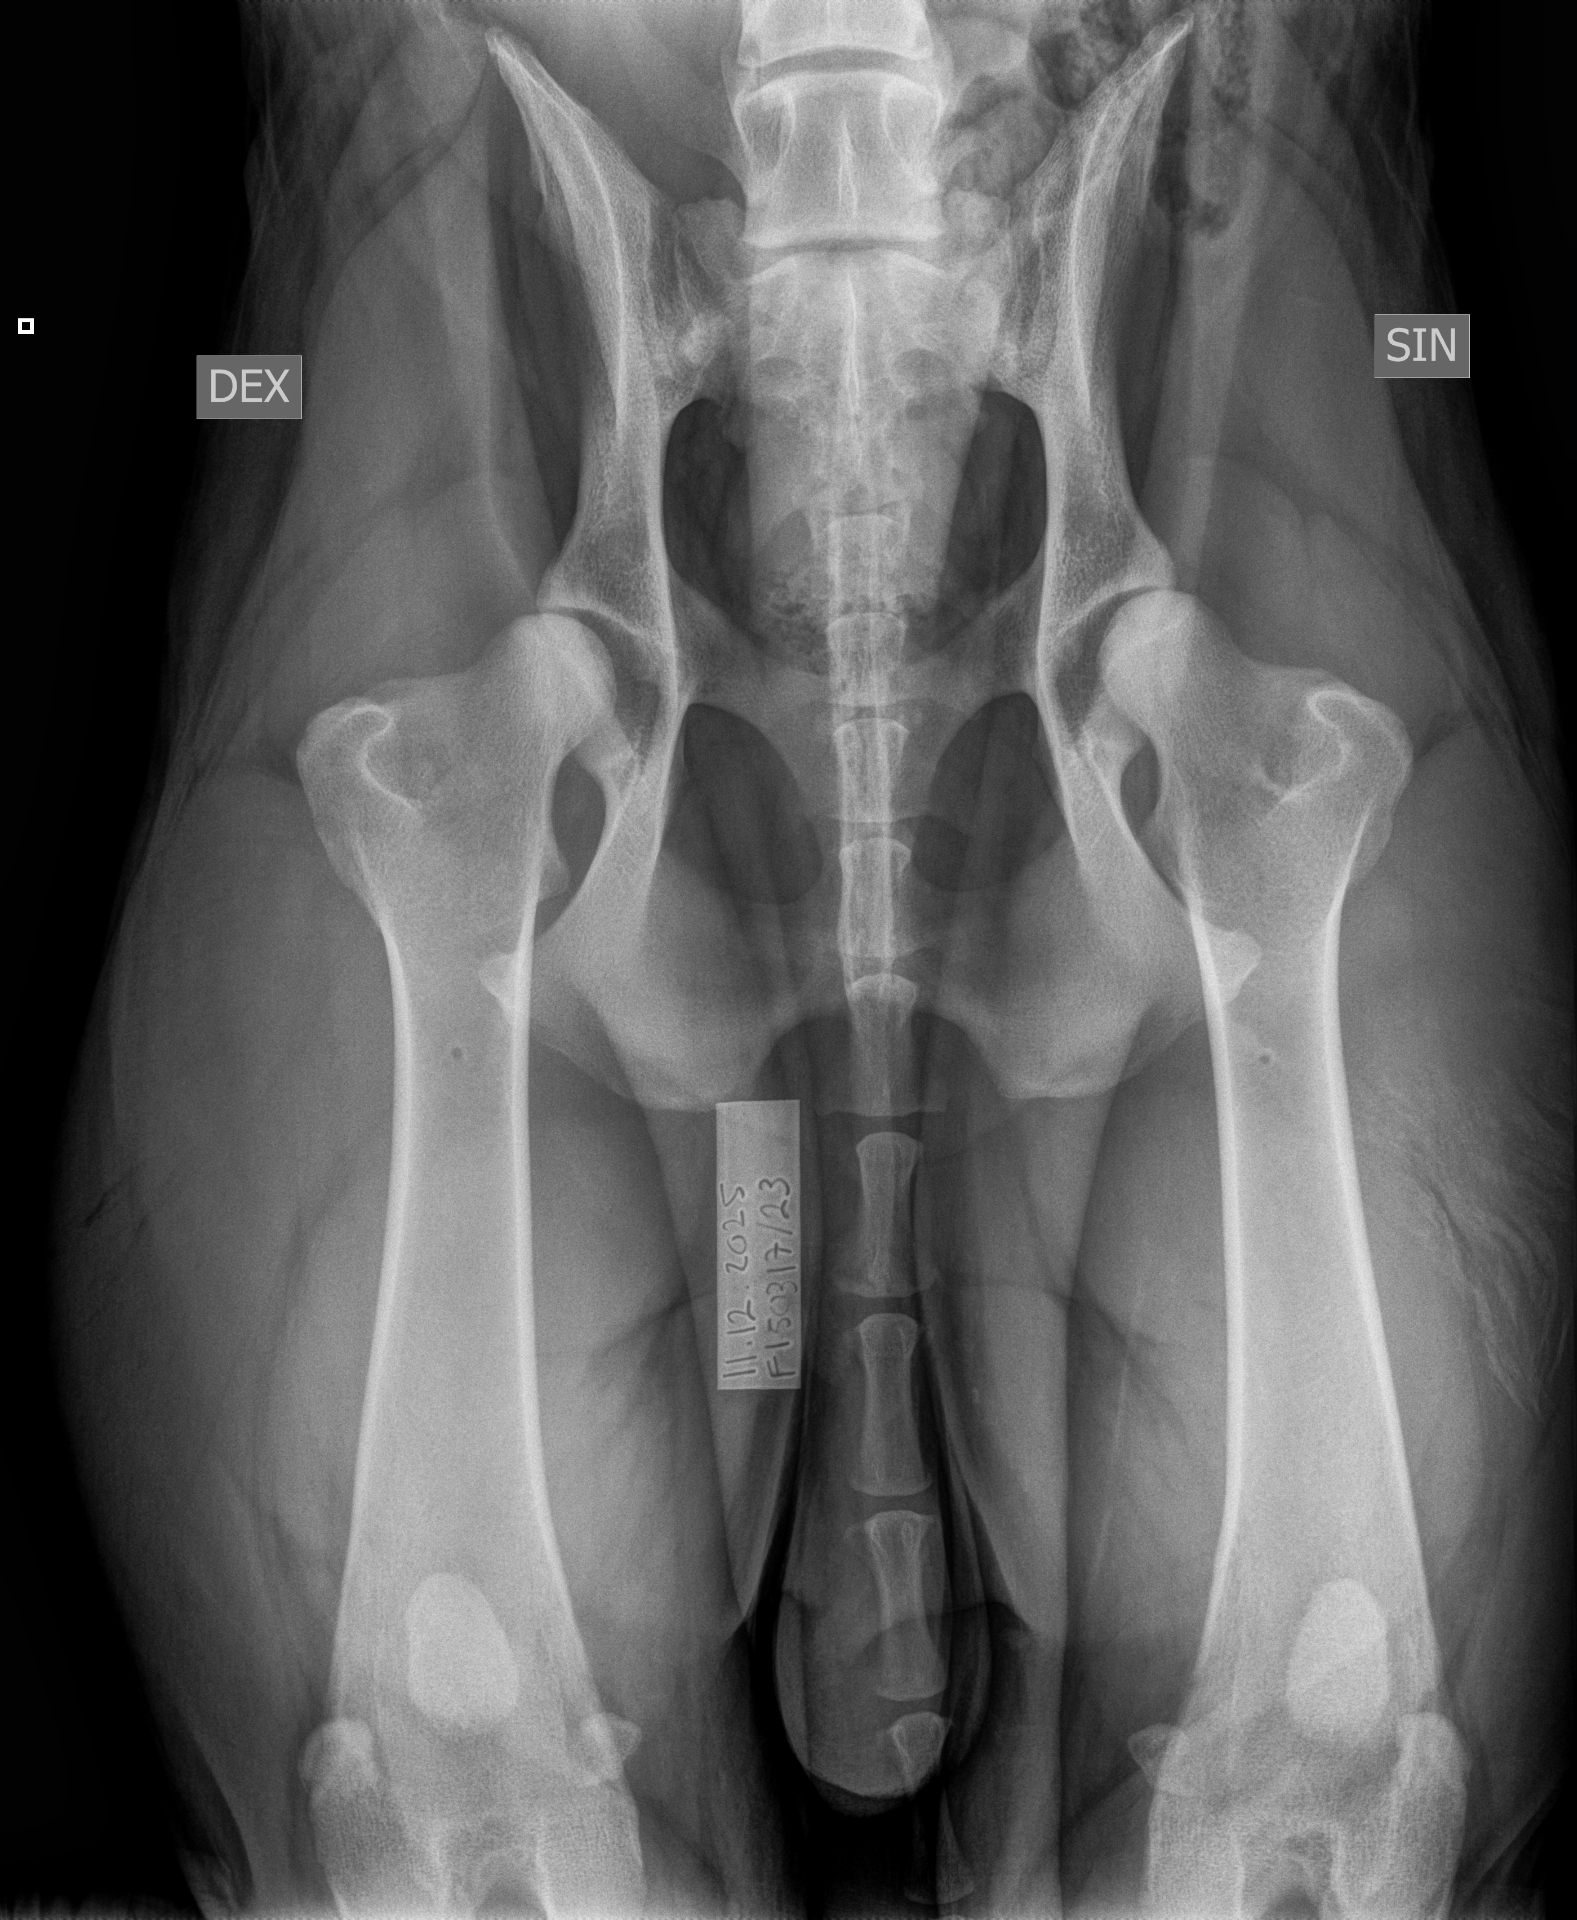

| 12.12.2025 | kyynärniveldysplasia lonkkaniveldysplasia | 0/0 D/D |

| 14.12.2025 | selkälausunto nikamien epämuotoisuus selän spondyloosi välimuotoinen lanne-ristinikama | VA1 (Aste 1, lievä), lukumäärä: 1 SP0 (Puhdas) LTV0 (Normaali) |